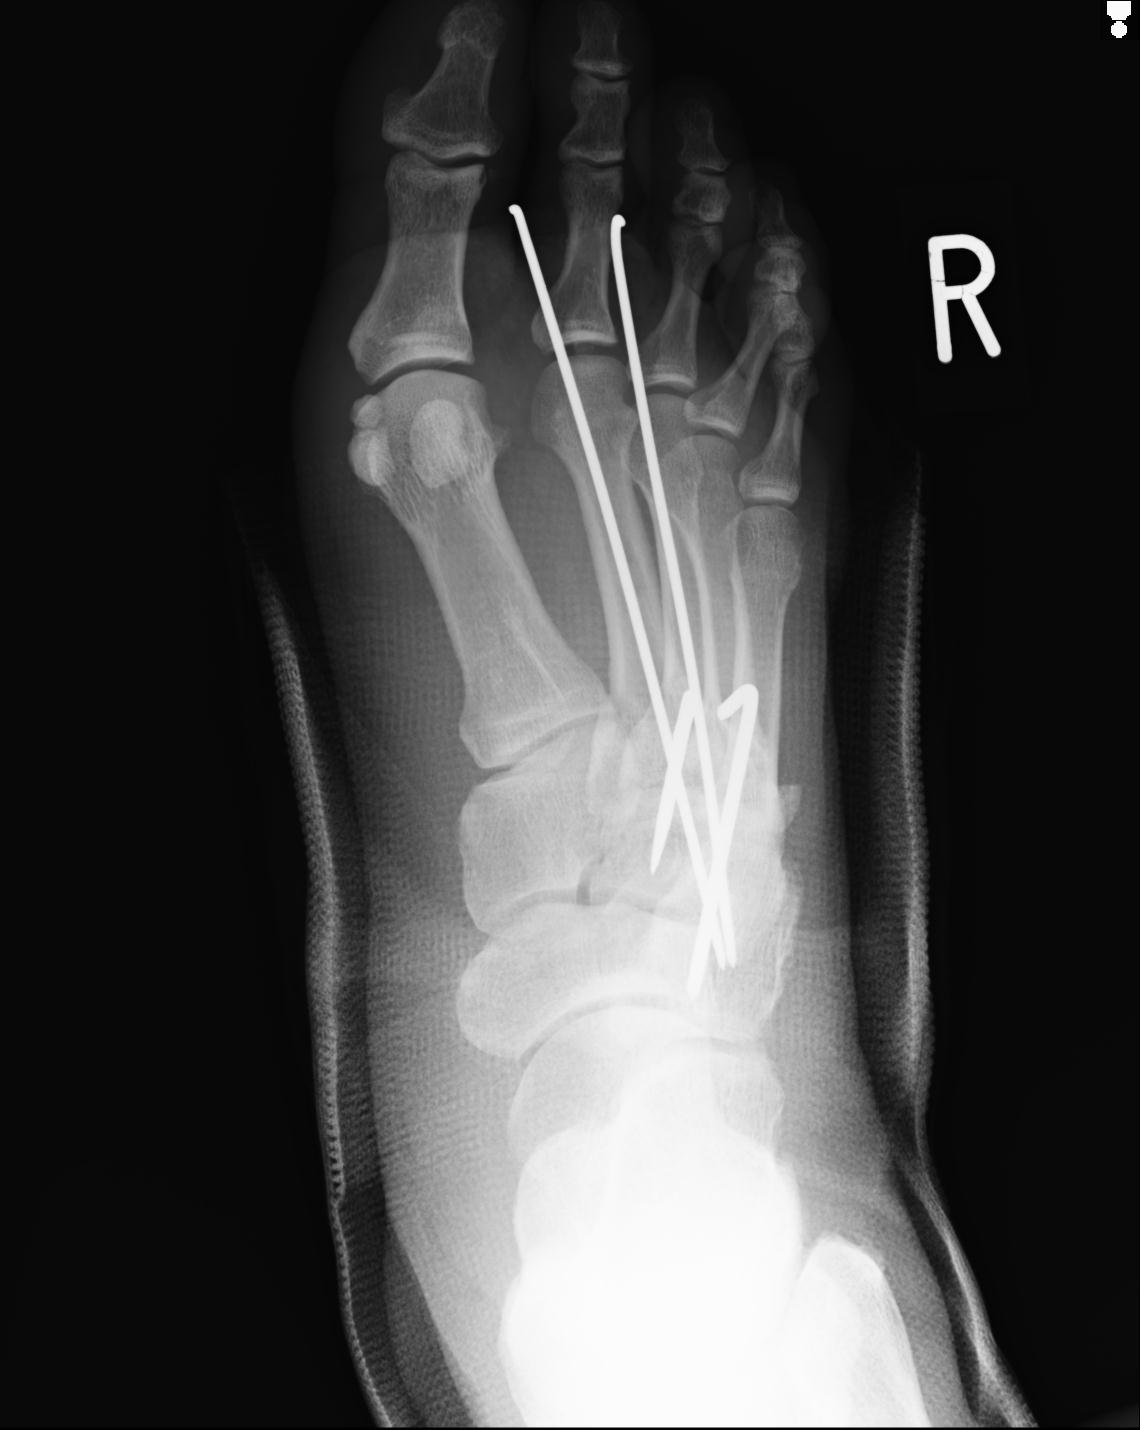

103177 3/11 右足 2R 3/16 右足 2R リスフラン脱臼 55歳男性